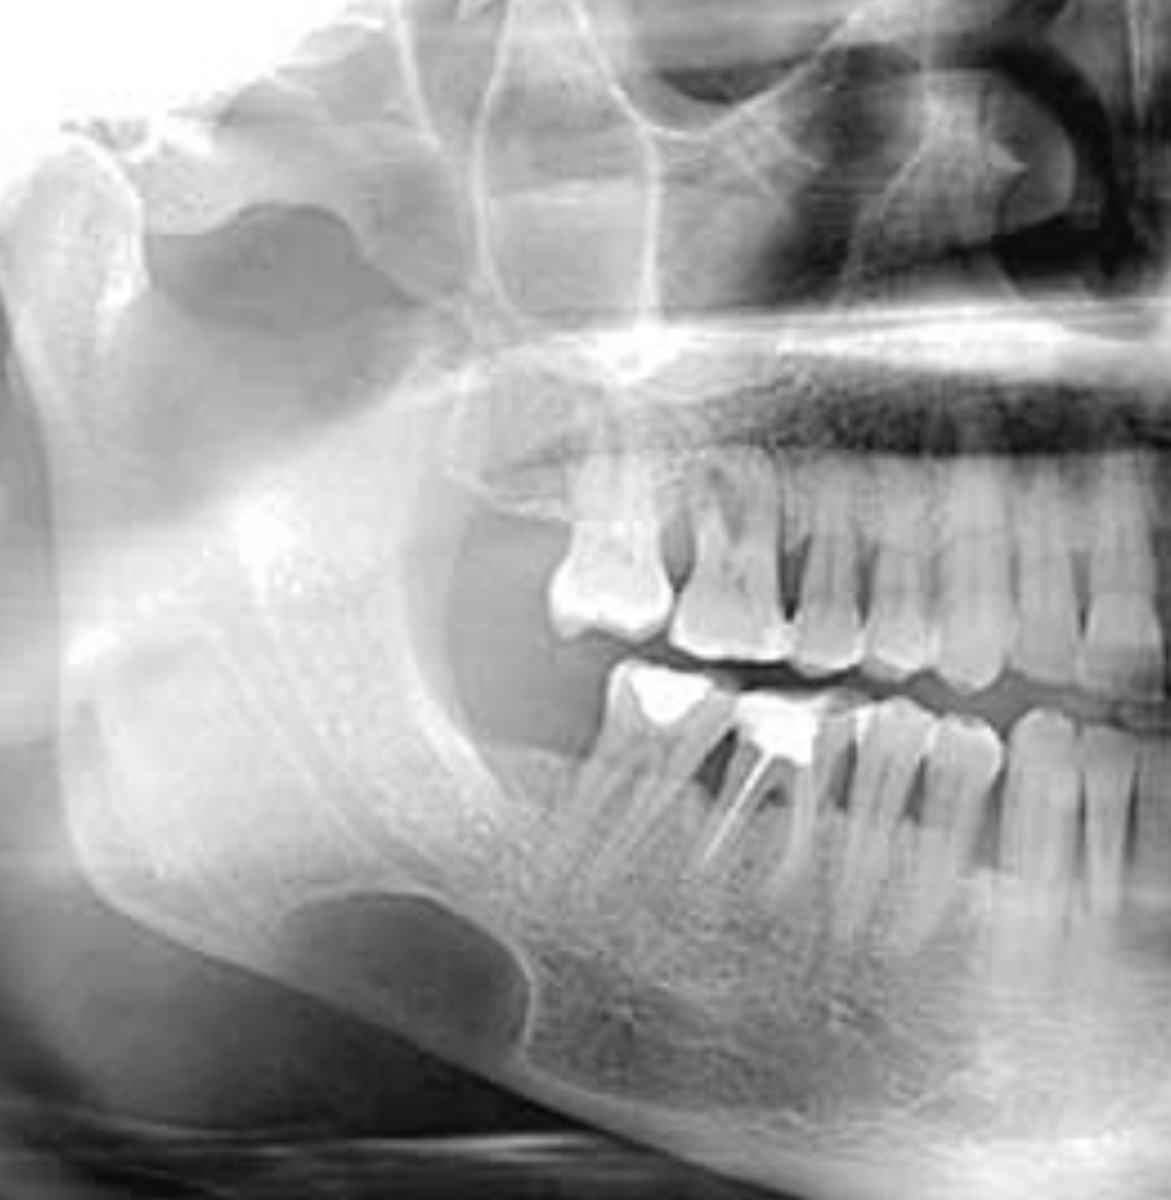

What are radiographic features of stafne bone cysts?

well-defined cyst-like radiolucency

1. anterior to angle of mand & inferior to mandibular canal

• unilateral or bilateral

radiolucent intraosseous lesion that is NOT lined with epitheium = NOT A TRUE CYST! **KNOW for exam

• also called Static Bone Cyst and Stafne Defect

developmental concavity containing normal salivary tissue on lingual aspect of posterior mandible

**KNOW FOR EXAM